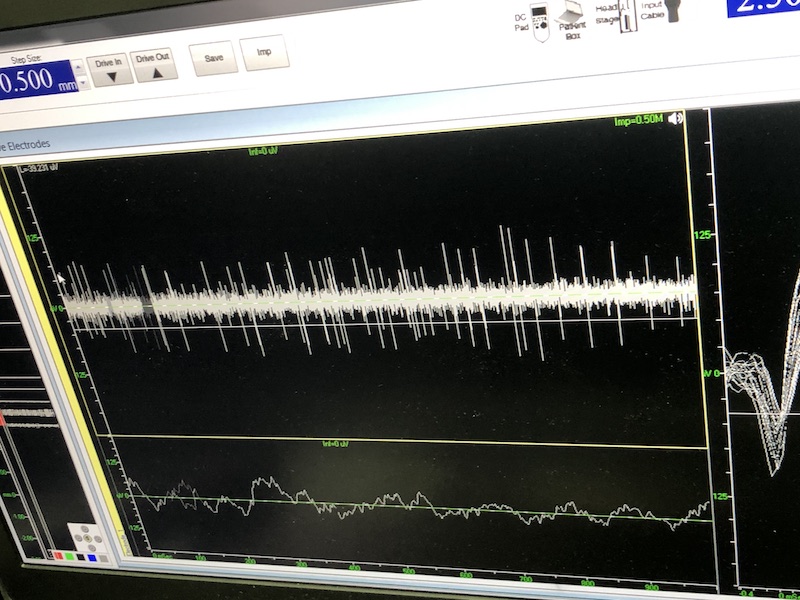

與此同時(shí),檢測(cè)電極實(shí)時(shí)記錄電極末端每一點(diǎn)處的電信號(hào),當(dāng)電極逐漸接近手術(shù)規(guī)劃靶點(diǎn)時(shí),借助電信號(hào)的特征,醫(yī)生可以判斷電極是否已經(jīng)沿長(zhǎng)軸植入患者顱內(nèi)的目標(biāo)核團(tuán),以及植入的準(zhǔn)確長(zhǎng)度。下圖中,檢測(cè)信號(hào)屬于典型的核團(tuán)信號(hào),證明電極已經(jīng)抵達(dá)相對(duì)理想的植入位置,記錄下此刻的位置后,即可在相應(yīng)位置植入刺激電極。